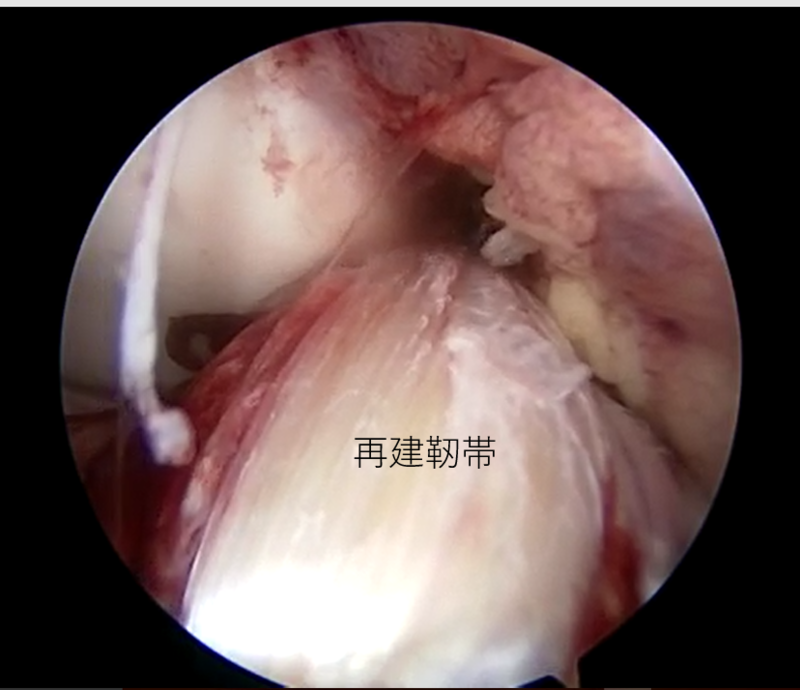

![]() |

| 外側半月板問題なし | 内側半月板問題なし | 再建靭帯 |